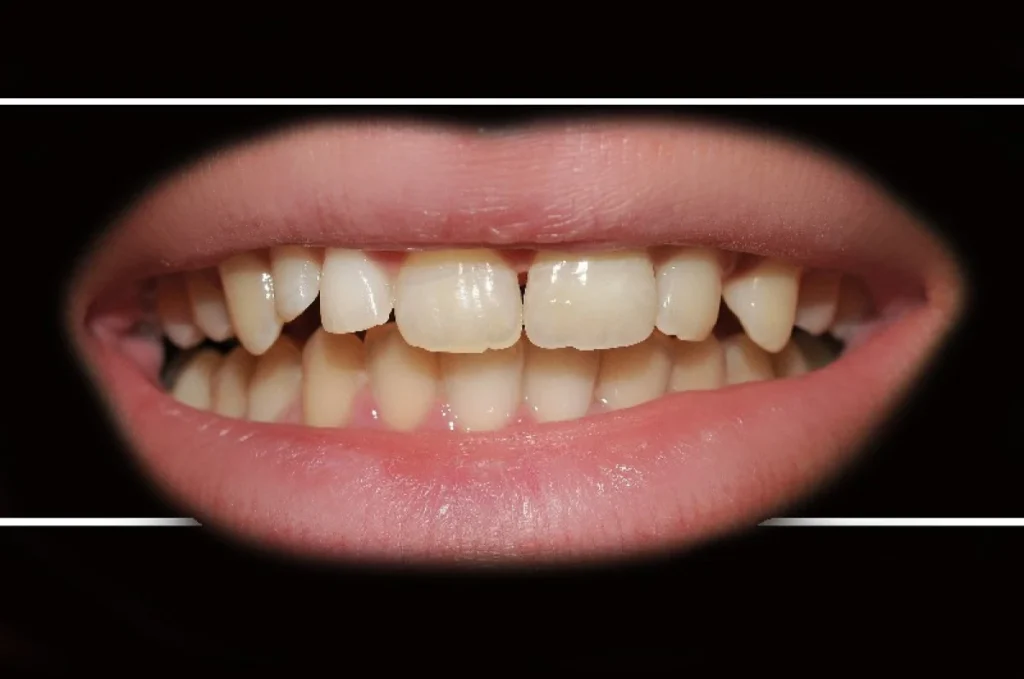

3. Les facettes dentaires esthétiques

La facette est une fine coque en céramique collée sur la face visible d’une dent. Elle est utilisée principalement pour des raisons esthétiques et permet de corriger l’apparence des dents de manière peu invasive.

Les facettes sont indiquées pour :

- Corriger une coloration persistante résistante aux techniques de blanchiment

- Améliorer l’aspect d’une dent usée, abîmée ou légèrement fracturée

- Harmoniser la dentition lorsqu’il existe de petits désalignements

Très fines et translucides, elles offrent un rendu naturel et permettent de redonner confiance au patient, tout en préservant l’intégrité de la dent.

La prothèse conjointe ne se limite pas à restaurer la fonction masticatoire. Elle contribue aussi fortement à l’esthétique et au bien-être psychologique. Retrouver un sourire harmonieux redonne confiance au patient, tant dans sa vie personnelle que professionnelle.

Nous attachons donc une attention particulière à l’intégration esthétique de chaque prothèse. La forme, la teinte et la translucidité sont soigneusement étudiées pour s’harmoniser avec les dents naturelles et offrir un rendu discret et naturel.